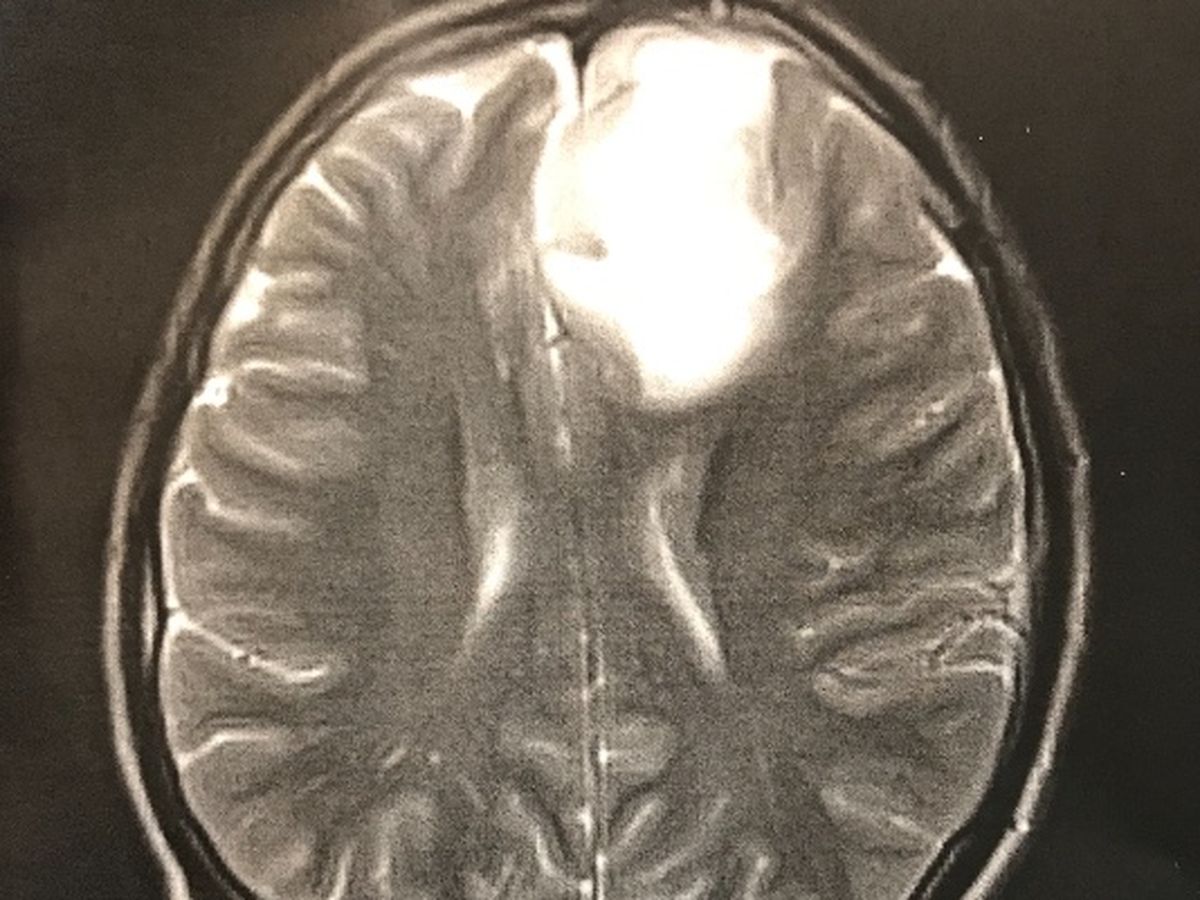

I am starting this for my brother Josh. When Josh was 9 years old he was diagnosed with Type 1 diabetes. He has been in and out of the hospital his whole life. He struggles daily with neuropathy and dealing with his blood sugar. But my brother has always been hard working even when he is in a great deal of pain and would give anyone the shirt off of his back. But last week, things changed. On September 29th, Josh had two seizures back to back while he was at work. He was taken by ambulance to Freeman Hospital in Joplin. There we found out what was causing the seizures. It is a brain tumor. That was the scariest phone call I’ve ever received. Josh will have surgery on October the 10th to have the tumor removed. At this point, they do not think it is cancer. THANK YOU JESUS! But it will be sent off so we will know for sure know what it is and what is causing it after it has been removed. Right now Josh is unable to work and will be unable to work after the surgery for quite some time. I’m starting this campaign to help with his medical expenses, back and forth trips to the Drs and his bills he is unable to pay while he is not working. Most of all, we just want prayers. Prayers that the tumor is 100% not cancer! Prayers that he makes it through the surgery without any complications, and prayers that his recovery is smooth, so he can go back to being a 23 year old young man living his life. But if you can donate, even a $1, I know he would appreciate it. Thank you all for all of the love you have shown us already. Please keep the prayers coming, we appreciate it more than you know. We love Josh so incredibly much and just want to see him well and living his life. Thank you.